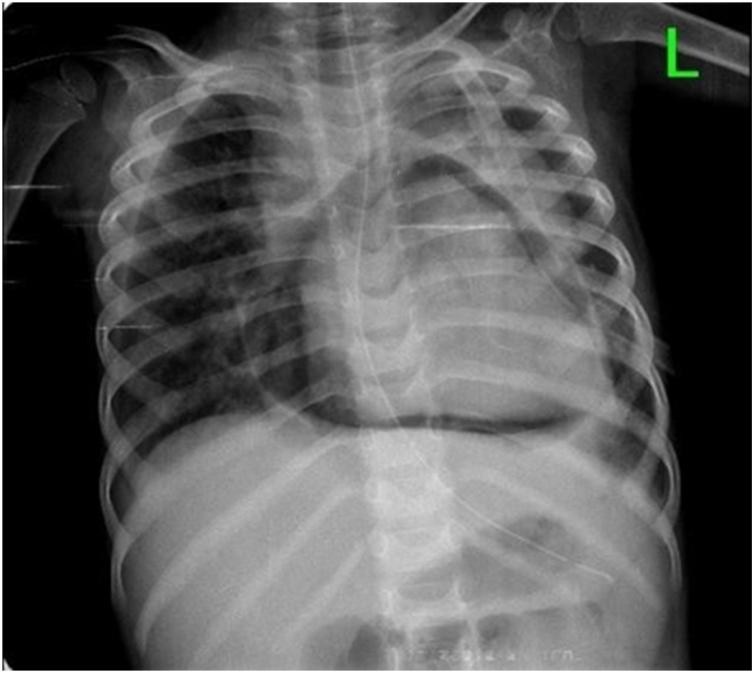

We present a rare case of iatrogenic pneumopericardium in a 1 year and 7 months old female child for whom a left side tube thoracostomy was done using nasogastric tube for an indication of left empyema thoracis. Later, she developed progressively worsening shortness of breath and imaging revealed iatrogenic pneumopericardium. She was managed conservatively and discharged home in good condition.

Iatrogenic pneumopericardium can have a range of presentations from being asymptomatic to features of cardiac tamponade. Patient management depends on the presence of tamponade effect and age of the patient. Infants tend to develop cardiac tamponade earlier urging surgical intervention but selected patients can be managed conservatively.